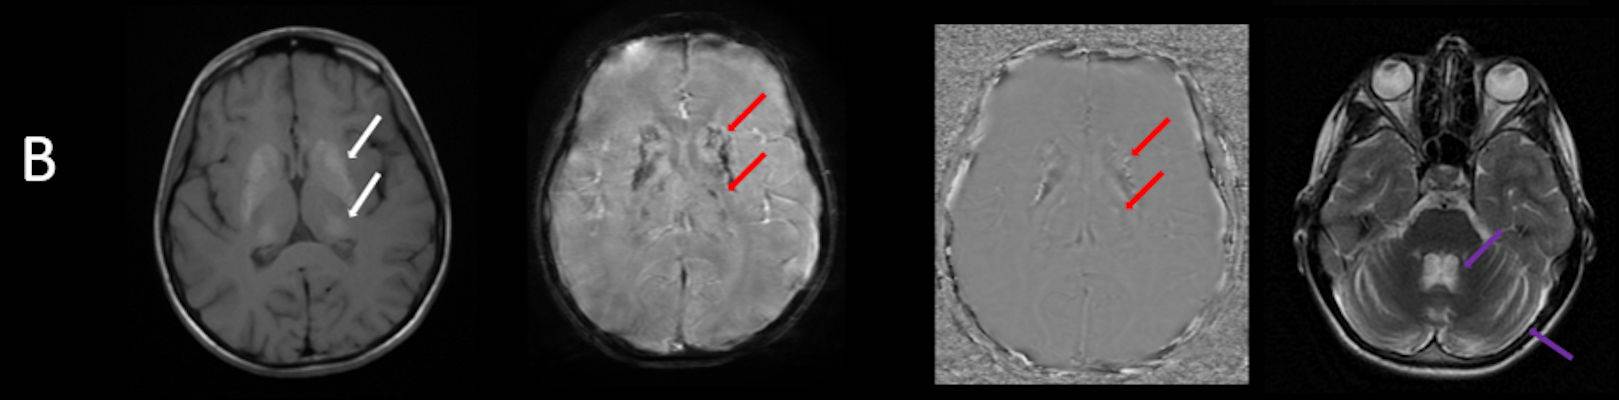

- B) Aksiyel T1A görüntülerde her iki lentiform ve kaudat nukleuslarda, talamuslarda simetrik hiperintensite (oklar) izleniyor. Bu düzeyde tariflenen sinyallerin SWI ve faz görüntülerde kalsifikasyon ile uyumlu olduğu görülmektedir (oklar). T2A görüntüde yaş ile uyumsuz serebellar atrofi ile uyumlu foliada derinleşme ve 4. ventrikül genişliğinde artış izlenmektedir (oklar).

- BT’de birden fazla lokalizasyonda multipl enfarkt benzeri odaklar ve özellikle ileri yaş hastalarda belirginleşen bazal gangliyon kalsifikasyonları izlenebilir. Lezyonlar çoğunlukla pariyeto-oksipital ve pariyeto-temporal bölgelerde yoğunlaşır ve serebral atrofi eşlik edebilir.

- Subakut dönemde kortikal laminar nekrozu temsil eden “Black toenail sign” bulgusu görülebilir.